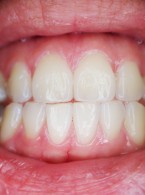

Leczenie techniką regeneracji wgłobionego zęba przyczynowego ropnia dołu nadkłowego

Zobacz więcej

Agnieszka Wal‑Adamczak